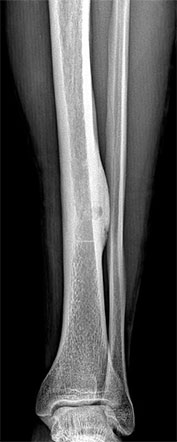

Bone tumors are rare lesions. A large part of these tumors are benign lesions, and they often occur by chance during radiological examinations for another reason. As a complaint, they usually show swelling and pain. Rarely, it is diagnosed after causing a fracture in the place where it was. Osteoid osteoma, osteochondroma (exostosis), enchondroma, non-ossifying fibroma, eosinophilic granuloma, simple bone cyst, fibrous dysplasia and intraosseous lipoma/ganglion are the most common lesions of benign tumors.